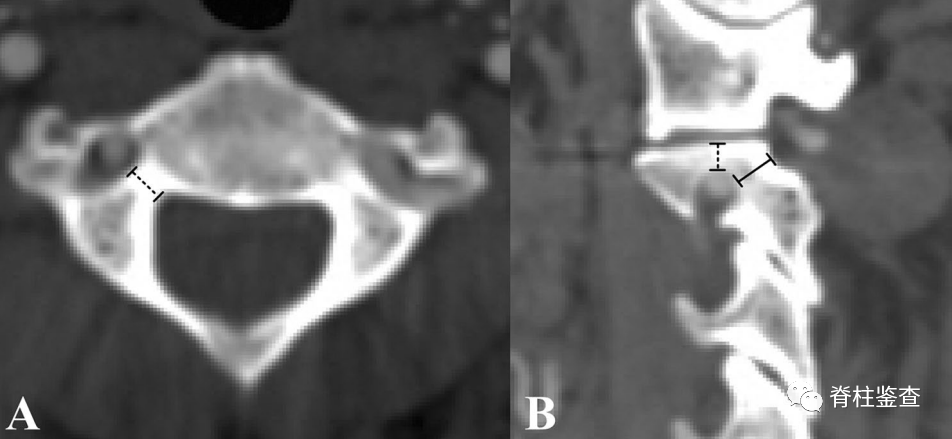

椎弓根狭窄(A)和椎动脉高跨(B)

B:椎弓根狭窄,椎动脉高跨右侧椎弓根螺钉置入风险高

B:椎弓根狭窄,右侧椎动脉高跨